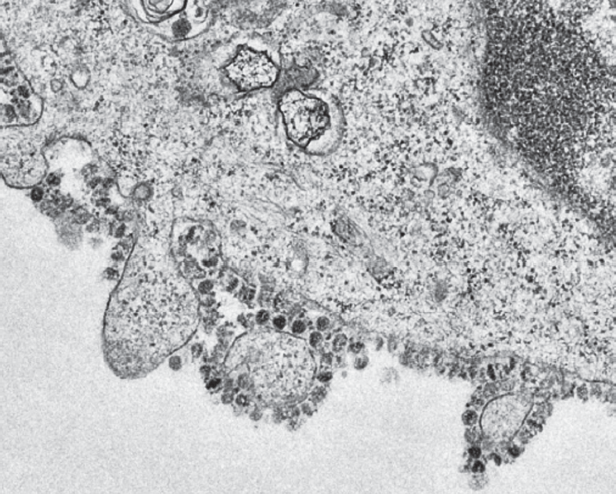

Вирус прикрепляется к клетке с помощью поверхностных белков, затем «продавливает» клеточную оболочку и вводит в ее цитоплазму свою РНК. Далее запускается сборка вирусных белков. После формирования вирусного нуклеокапсида готовые вирусы покидают клетку, используя ее внешнюю мембрану, а сама клетка погибает (рис. 2). В большинстве случаев данный процесс самостоятельно ограничивается, что приводит к полному выздоровлению по мере формирования защитных антител в организме.

Рис. 2. Формирование вирионов коронавируса (электронная микроскопия, университет Гонконга, 2019)

Fig. 2. Coronavirus Virion Formation (Electron Microscopy, University of Hong Kong, 2019)